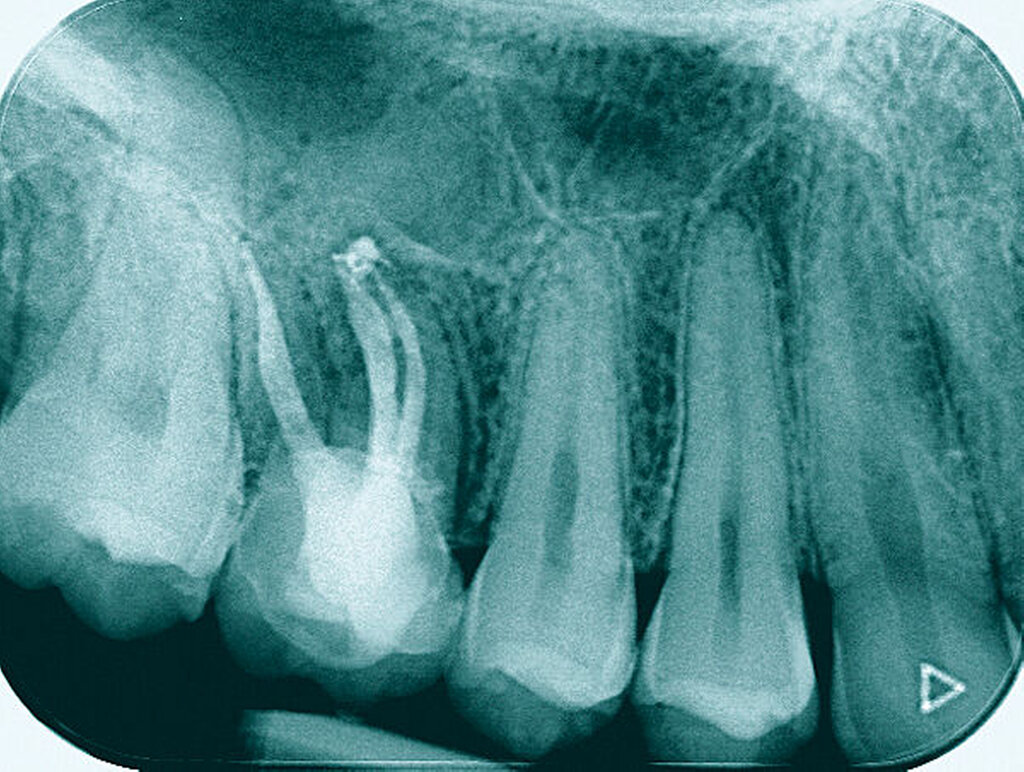

Eine 53-jährige Patientin stellte sich 2015 mit plötzlich aufgetretenen, starken Beschwerden an Zahn 16 und der Bitte um Abklärung vor. Es erfolgte die klinische und röntgenologische Befundung des Zahnes, der neben einer apikalen Parodontitis auch eine große, fast bis in die Furkation reichende Kronenrandkaries an der mesiobukkalen Wurzel aufwies. Um diesen vorhersagbar versorgen zu können, wurde der Patientin die endodontische Behandlung mit Amputation der mesiobukkalen Wurzel und anschließender Versorgung mittels Vollkrone als Alternative zur Extraktion aufgezeigt. Sie entschied sich für den Zahnerhalt.

So folgte nach der Wurzelfüllung die Amputation der mesiobukkalen Wurzel. Der Zahn wurde nach der Amputation auf Wunsch der Patientin zunächst mit einem Langzeitprovisorium versorgt, das im Verlauf gegen eine definitive Versorgung ausgewechselt wurde. Die Patientin ist seitdem an 16 beschwerdefrei, der Zahn ist stabil und hat eine gute Langzeitprognose.